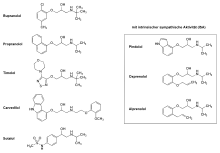

Beta-blockers

Beta-blockers are competitive antagonists of the adrenergic beta receptor, blocking the binding sites of epinephrine and norepinephrine. They lower blood pressure by a RAAS independent mechanism, reducing plasma renin activity and Ang II levels. Propranolol, Atenolol, Bupranolol, Timolol, are some examples of clinically available beta-blockers.